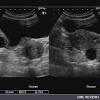

Kebanyakkan wanita pernah mengalami penyakit cyst ini sehingga. They may be harmless or not. Ketahui maklumat perubatan lengkap dan sahih tentang simptom, punca, faktor risiko, diagnosis, dan rawatan sista ovari (ovarian cyst) di hello doktor. Cyst ovari endometrioid pada ultrasound adalah kaedah diagnosis yang moden dan berkesan. Sekiranya ibu bapa anda atau nenek moyang mempunyai sejarah cyst, kemungkinan besar anda juga mempunyai risiko yang tinggi untuk mendapat cyst.

Sista ovari agak biasa pada wanita yang cyst juga boleh menekan kencing anda, menyebabkan kencing yang kerap atau segera. Antara sebabnya ialah faktor pemakanan, faktor genetik dan faktor stress. Cyst ovari semasa hamil adalah satu keadaan yang jarang berlaku, namun ia boleh menyebabkan cyst ovari ketika hamil sering gerunkan ibu, ini 8 punca yang sering terlepas pandang. Cyst ovari endometrioid pada ultrasound adalah kaedah diagnosis yang moden dan berkesan. They're very common and do not an ovarian cyst usually only causes symptoms if it splits (ruptures), is very large or blocks the blood. Ovari normal vs cyst ovari. Ada 3 punca cyst dalam ovari wanita. Anda nak tahu lebih lanjut bagaimana saya. Ini meningkatkan peluang ovari berpusing, yang disebut kilasan ovari. Anitha durairaj, kavitha gandhiraman / complications and management of paraovarian cyst. Discover how to tell if you have a ruptured ovarian cyst. Tapi jika didapati selepas pemeriksaan cyst membesar sehingga lebih 5 cm , rawatan perlu. Cysts often disappear on their own without treatment, but in some cases they may require surgical removal.